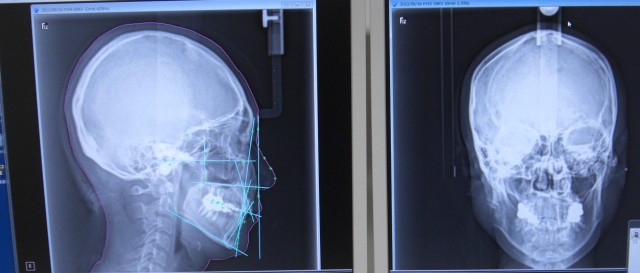

矯正治療に必要不可欠なものは、セファロ分析です。

最初に分析・診断を正確に受けてください。

特に小児では絶対に必要なことです。

これからの成長発育があるからです。

矯正治療の途中で、もう一度セファロ分析し直すことあります。

最初の分析・診断によって抜歯矯正か非抜歯矯正で治るのかわかります。

また、正確に診断・分析をすることで、どの歯を抜歯して、

どのように歯を動かしていくのが理想的に治るのかを設計をすることができます。

次は診断分析のミス、もしくは最初から分析無しで矯正を進めていった場合です。